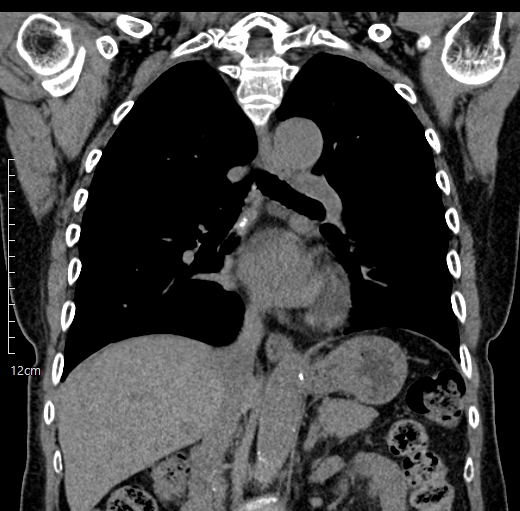

CT와 MRI 영상은 일반적인 사진과는 전혀 다릅니다. 흑백으로 구성된 단면 영상 속에는 수많은 인체 구조물들이 겹쳐 보이고, 각 조직의 밀도나 신호 강도에 따라 색이 다르게 나타납니다.

예를 들어, MRI 영상에서는 종양처럼 보이는 음영이 실제로는 혈관이나 정상 해부학 구조일 수 있으며, CT에서는 정상적인 석회화가 병변처럼 보일 수도 있습니다.

이러한 이유로 영상의학과 전문의는 최소 10년 이상의 교육과 수련을 통해 각 부위의 정상 해부 구조와 병적 소견을 구분하는 능력을 갖추게 됩니다.